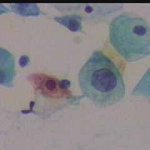

Εικονες φυσιολογικών και παθολογικών κυττάρων ενδοτραχήλου κι ενδομητρίου στο επίχρισμα κατά Papanicolaou. Περιστατικά ιατρείου. Παρατίθενται για τις ανάγκες επίδειξης περιστατικών στο forum του www.gyn.gr, για φοιτητές εργαστηριακών παραϊατρικών επαγγελμάτων και για καθε άλλο ενδιαφερόμενο.